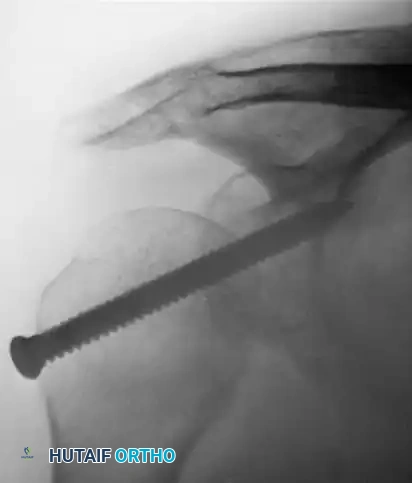

- Neer Modification: Neer advanced this concept by performing an osteotomy of the lesser tuberosity. The subscapularis tendon, with its attached bone block from the lesser tuberosity, is mobilized and rigidly fixed into the anterior defect using a cancellous screw. This provides superior bone-to-bone healing compared to tendon-to-bone healing.

- Swiss Screw Fixation: As described by Neviaser, a large Swiss screw can be driven through the acromion directly into the humeral head to maintain reduction.

- Kirschner Wire Fixation: The Wilson and McKeever method utilizes two heavy, crossed Kirschner wires driven through the acromion into the humeral head to stabilize the joint after the reduction of a posterior dislocation.